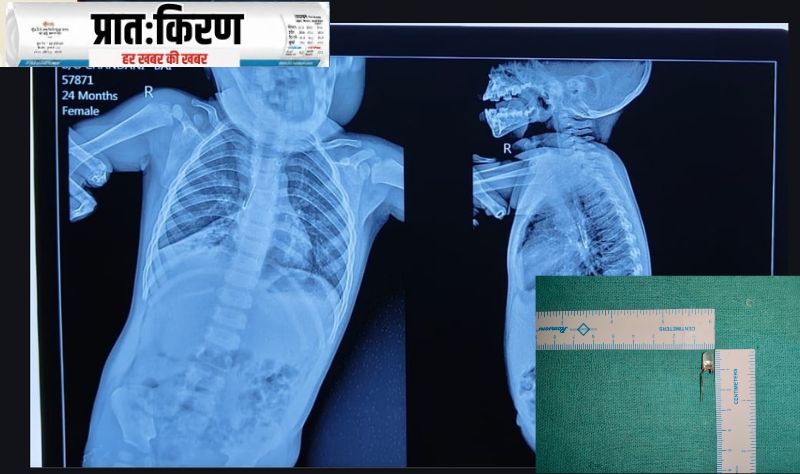

चिकित्सा के क्षेत्र में एक अद्भुत सफलता दर्ज करते हुए, नेताजी सुभाषचंद्र बोस मेडिकल कॉलेज एवं अस्पताल (NSCB Medical College, जबलपुर) के चिकित्सकों ने एक नन्ही जान को नई जिंदगी दी है। दमोह जिले की 17 माह की बच्ची गरिमा हिरा सिंह के फेफड़ों की मुख्य श्वसन नली में फंसी एलईडी लाइट को डॉक्टरों ने कुशलता से निकालकर उसकी जान बचा ली। विशेषज्ञ डॉक्टरों की तत्परता और टीमवर्क से बच्ची अब पूरी तरह स्वस्थ है और उसे डिस्चार्ज कर दिया गया है।

दमोह निवासी हिरा सिंह और चांदनी की पुत्री गरिमा को पिछले एक सप्ताह से लगातार खांसी की शिकायत थी। जब हालत बिगड़ी तो परिजन 25 अक्टूबर को मुरली मनोहर अस्पताल दमोह लेकर पहुंचे।यहां चेस्ट एक्स-रे में डॉक्टरों को शक हुआ कि बच्ची के फेफड़ों में कोई विदेशी वस्तु (Foreign Body) फंसी हुई है, जो सांस लेने में बाधा डाल रही थी। स्थिति को गंभीर देखते हुए, बच्ची को 26 अक्टूबर को NSCB मेडिकल कॉलेज, जबलपुर रेफर किया गया।

जबलपुर पहुंचने पर डॉक्टरों की टीम ने तत्काल ब्रोंकोस्कोपी (Bronchoscopy) करने का निर्णय लिया। जांच में पाया गया कि बच्ची के दाहिने फेफड़े की मुख्य श्वसन नली (Right Main Bronchus) में एलईडी लाइट फंसी हुई थी।इतनी छोटी बच्ची के नाजुक फेफड़ों से इस तरह की वस्तु निकालना बेहद जटिल और जोखिमपूर्ण था। बावजूद इसके, डॉक्टरों ने असाधारण कौशल का प्रदर्शन करते हुए एलईडी लाइट को सुरक्षित रूप से निकालने में सफलता प्राप्त की।